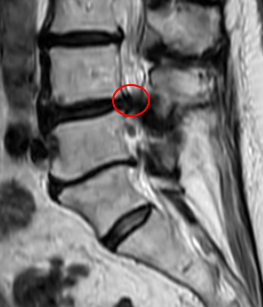

治療前

腰椎MRIの画像を確認したところ、赤い枠内のL4/5で脊柱管が狭窄しているのを確認しました。また「歩いて5分程度でより痛くなる」というお話しから間欠性跛行の症状が出ていると考えられます。

これらから、痛みの原因はL4/5部分の脊柱管狭窄症だと診断しました。